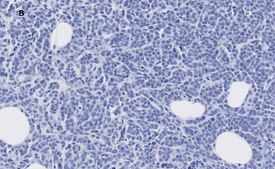

Immunohistochemistry (Paraffin) Analysis: A 1:100 dilution from a representative lot detected Insulin receptor substrate 1 in human breast cancer and human prostate cancer tissue sections.